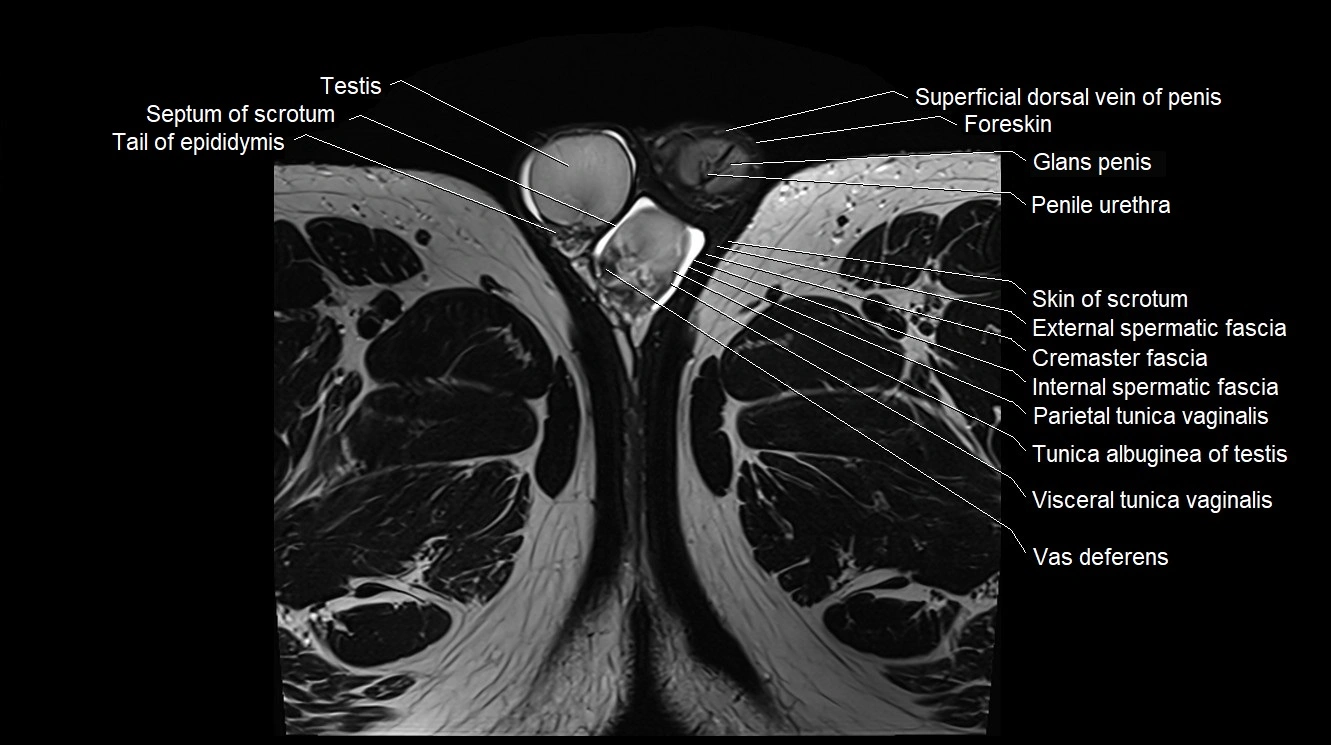

- Testis

- Septum of scrotum

- Tail of epididymis

- Cremaster fascia

- External spermatic fascia

- Internal spermatic fascia

- Parietal tunica vaginalis

- Tunica albuginea of testis

- Visceral tunica vaginalis

- Penile urethra

- Glans penis

- Foreskin

- Superficial dorsal vein of penis

- Vas deferens